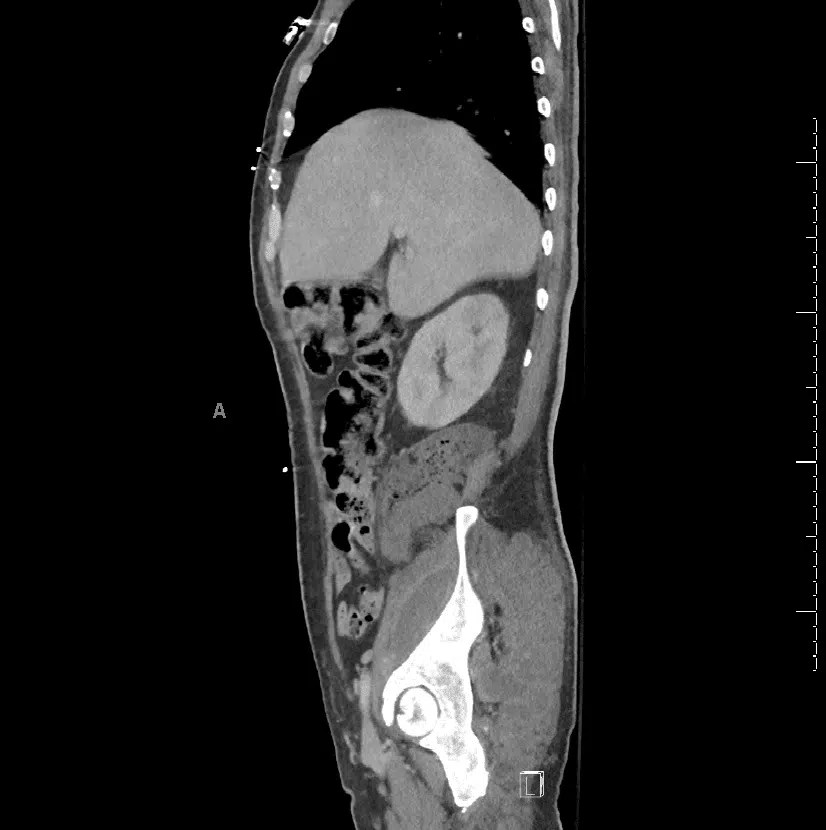

US and CT of patient with buttock abscess. Figure (A) demonstrates CT Abscess Gluteal Cleft Find out the risk factors,. Learn about the causes, symptoms, diagnosis and treatment of pilonidal disease, a condition involving hair penetrating the skin at the natal cleft. A pilonidal sinus (pns) is a small cyst or abscess that occurs in the cleft at the top of the buttocks. A pilonidal (abscess, cyst, sinus, dimple) is an abscess in the natal. Abscess Gluteal Cleft.